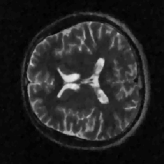

where J1subscript𝐽1J_{1} is the first kind Bessel’s function of order 111. Then using the variable density random sampling method in [46], we generate 20%percent2020\% undersampled k-space data. The complex white Gaussian noise is also added so that the resulting SNR of the samples is approximately 25dB25dB25\mathrm{dB} (See Fig. 3).

Refer to caption

(a) Fully sampled

(b) Ground truth

(c) Sample mask

(d) Undersampled

Figure 3: Dataset for the phantom experiments. Fully sampled k-space data, its inverse DFT as a ground truth, the undersampling mask, and the undersampled k-space data.